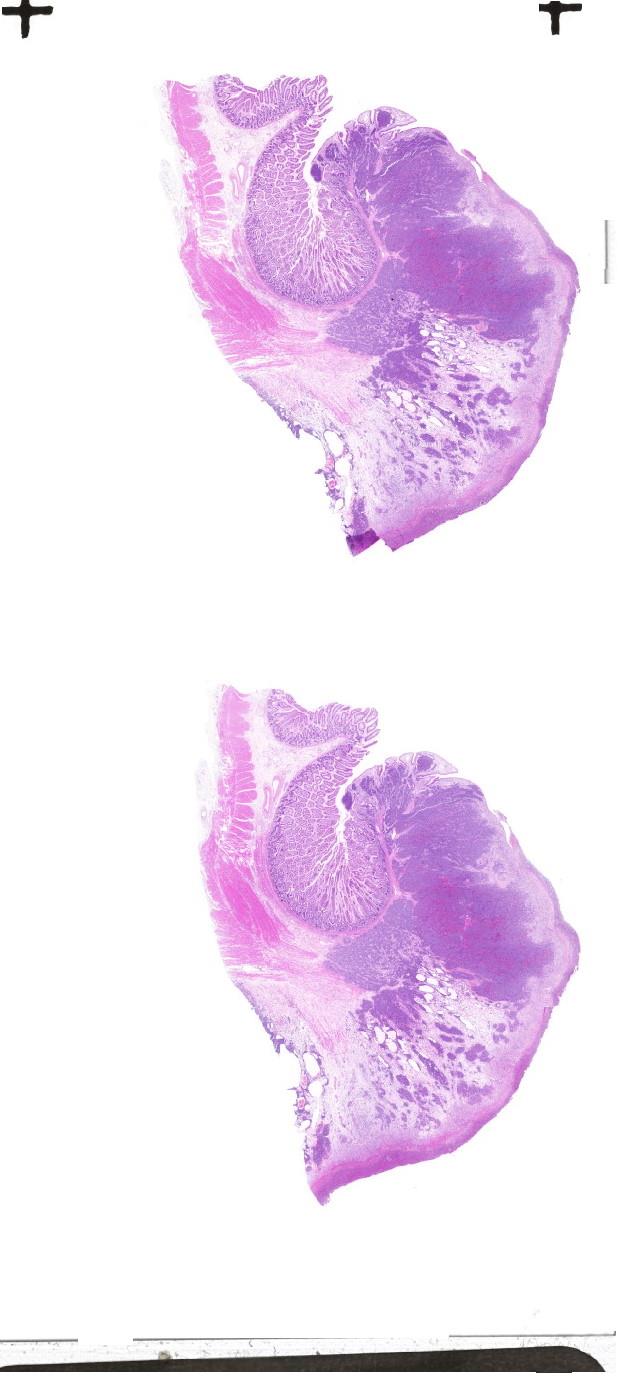

女, 62岁, “反复便血1个月”就诊。肠镜提示肛管-直肠交界处占位。 |

贵州中医药大学第一附属医院 |